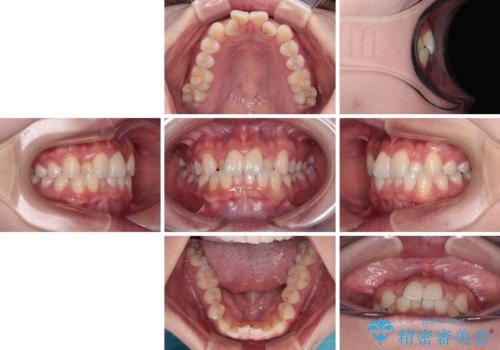

前歯のクロスバイト 裏側に隠れた歯をワイヤー装置で短期間治療

- 上顎前歯のクロスバイトを気にして来院された患者様です。

ワイヤー矯正でもマウスピース矯正でも対応可能でしたが、マウスピースによる自己管理に一切の自信がないとのことで、ワイヤー装置にて矯正治療を行うこととしました。

装置の外見を気にしていましたが、短期間で治療を終えることができるだろうと伝えると、安価であるメタルブラケットを選択されました。

想定通り、1年強で綺麗に仕上げることができました。